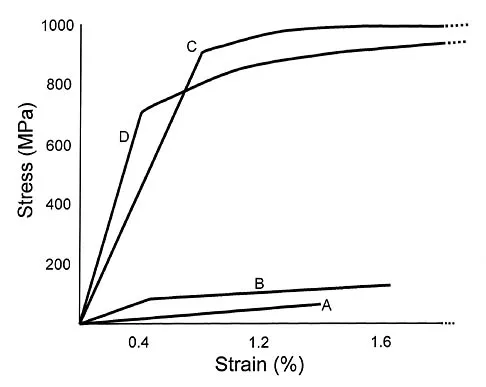

Vertebral fractures are common in the thoracolumbar spine. What is the most important factor that determines the strength of the cancellous bone in the vertebral body?

Explanation